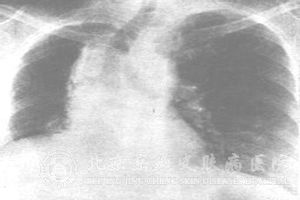

在进行胸部恶性肿瘤的放疗过程中可辐射到健康的肺组织而导致放射性肺炎的产生,对于放射性肺炎发生后所导致的病理改变是怎样的可能大家还不是很了解,下面就为大家解释一下。

通常在接受放疗后的一两个月可能会出现放射性肺炎的急性期病理变化,也有会发生在半年后的病例,常出现肺部的血管,尤其是毛细血管出现损伤,导致充血、水肿及*浸泣,肺泡的Ⅱ型*再生减少,淋巴管扩张并形成透明膜。

而在放疗过后九个月以后则可出现放射性肺炎的慢性期病理改变,出现肺泡的广泛性纤维化,肺脏同时有所收缩、毛细血管的内膜变厚并发生硬化、管腔变窄或者阻塞,会使得肺循环的阻力增高且肺动脉压力增高。同时,炎症变化基纤维化亦可能导致胸膜变厚;由于细支气管粘膜上皮的间变和肺中发生的感染都可增加放射性纤维化的发展。